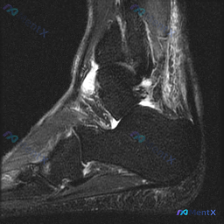

这是足踝部MRI冠状位T2加权序列,显示中后足交界区冠状面,可见距骨、跟骨、舟骨等骨性结构,中心区域是足底肌肉肌腱软组织结构。图像对比度良好,能清晰区分各层结构。

影像异常发现

- 定位:异常信号位于足底深部肌肉群(考虑足底短肌群或跖方肌区域)、部分肌腱附着处以及周围筋膜间隙

- 信号特征:多发斑片状、结节状高信号,信号强度接近液体,不均匀分布,伴随周围软组织水肿,边界模糊呈弥漫性浸润,和周围正常肌肉分界不清

- 其他表现:没有明显局限性占位效应,但区域组织纹理紊乱;骨质没有明显破坏或骨折,本次影像未发现明确的关节软骨异常信号,问题出在软组织。